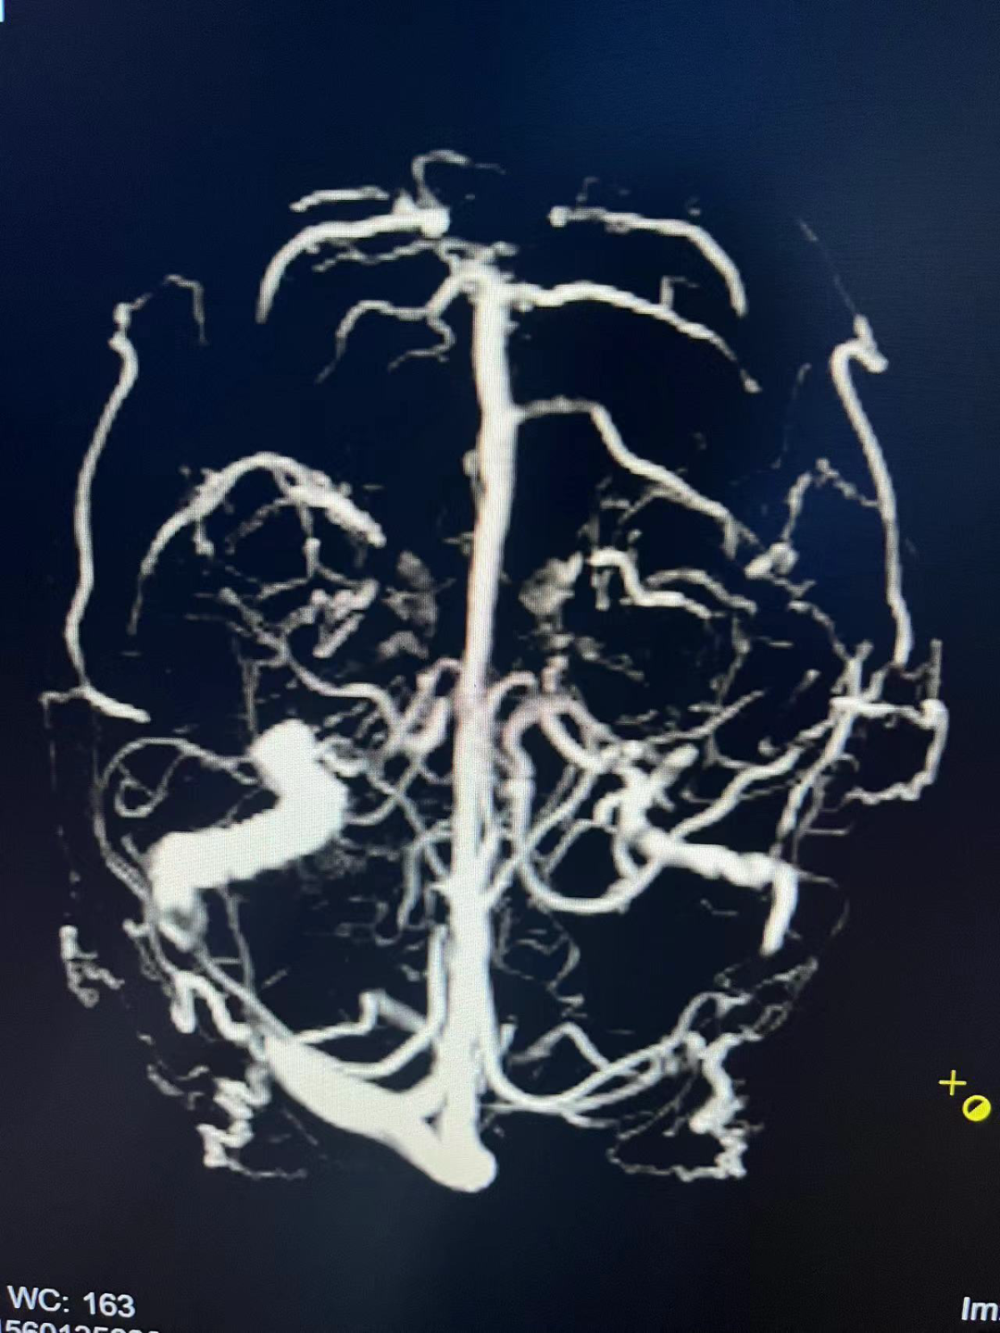

患者术前MRV显示

术前MRV显示:左侧横窦闭塞,右侧横窦和乙状窦交界处存在狭窄。术中造影进一步明确为右侧横窦乙状窦交界处重度狭窄,狭窄程度>70%,同时左侧横窦闭塞,乙状窦纤细,与术前MRV结果相符。术中测压,经粗略计算,狭窄处近、远端压力差约为10mmHg。术中进行球囊扩张,支架置入术后造影显示,静脉窦狭窄处成形良好,可见清晰的金属支架影。